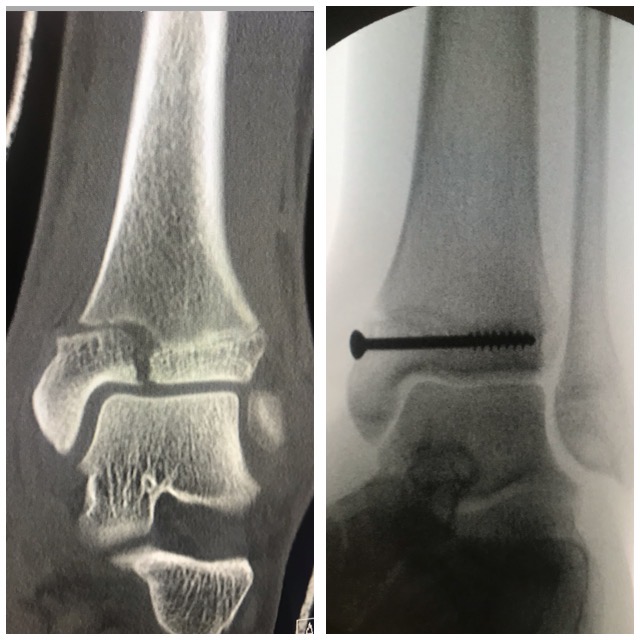

Nilkkamurtuma

Ennen – jälkeen